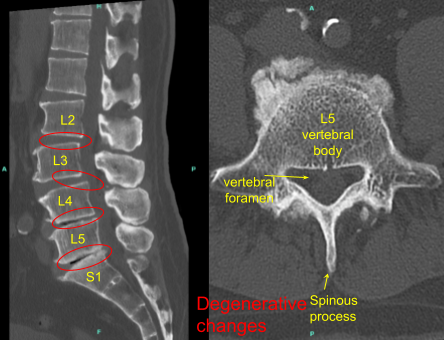

They got an MRI done which showed degenerative changes from L2 to S1 with retrolisthesis in L2-L3, grade 1 anterolisthesis at L3-L4, vacuum phenomena at L4-5 and L5-S1 with loss of disc space at L4-L5 and L5-S1.

We discussed treatment options and having failed all conservative management, the patient agreed for operative management in the form of L2 to S1 lumbar decompression and fusion.